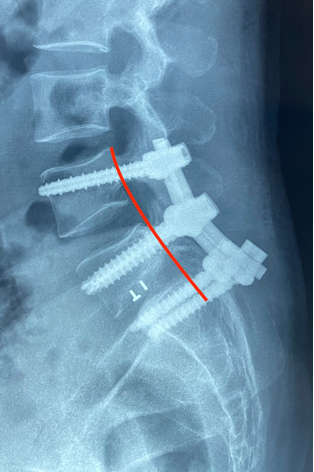

Ths.Bs Trần Đức Duy Trí, một chuyên gia trong lĩnh vực phẫu thuật cột sống tại Bệnh viện Hoàn Mỹ ITO Đồng Nai đã thực hiện ca phẫu thuật với sự tận tâm cùng ekip phẫu thuật. Đối mặt với những thách thức nguy cơ cao về liệt sau phẫu thuật do tổn thương nghiêm trọng tại đốt sống L5, ca phẫu thuật kéo dài hơn 3 giờ, Ths.Bs Duy Trí đã tiến hành bắt vít cuống cung cố định nẹp dọc từ L4-S1 và nắn trượt đốt sống, giải áp rễ và bao màng cứng. Nhờ sự kết hợp giữa tài năng của đội ngũ bác sĩ và sự hỗ trợ của máy C-Arm trong mổ, ca phẫu thuật đã đạt được thành công ngoài sự mong đợi. Chỉ sau một ngày, người bệnh đã có thể di chuyển đi lại và giảm đau vùng lưng và chân.

X-Quang trước và sau phẫu thuật

Ths.Bs Duy Trí chia sẻ: “Trượt thân sống độ IV rất nguy hiểm, đây là một ca phẫu thuật rất khó và phức tạp nguy cơ tổn thương rễ thần kinh trong khi mổ cao. Do trượt độ IV nên các cấu trúc giải phẫu bị biến đổi nhiều nên việc bắt vít cuống cung cũng có nhiều khó khăn. Mỗi ngày, chúng tôi rất hạnh phúc và tự hào khi thấy người bệnh của chúng tôi hồi phục và trở lại cuộc sống bình thường.”